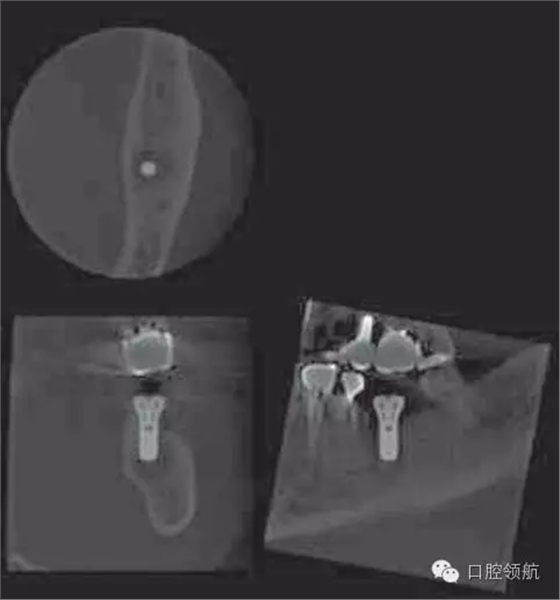

懷疑是因為植入術(shù)前進行5 根管治療導致的根尖周炎,拍攝牙片,根尖部未見異常,也沒有叩痛等癥狀(圖4)。

圖4 術(shù)后第14天拍攝的牙片。

術(shù)后第18天,進行CBCT的確認(圖5),種植體周圍發(fā)現(xiàn)不透過影像,而且種植體有松動,因此在浸潤麻醉下拔除(圖6~圖8)。

圖5 術(shù)后18天CBCT的影像。